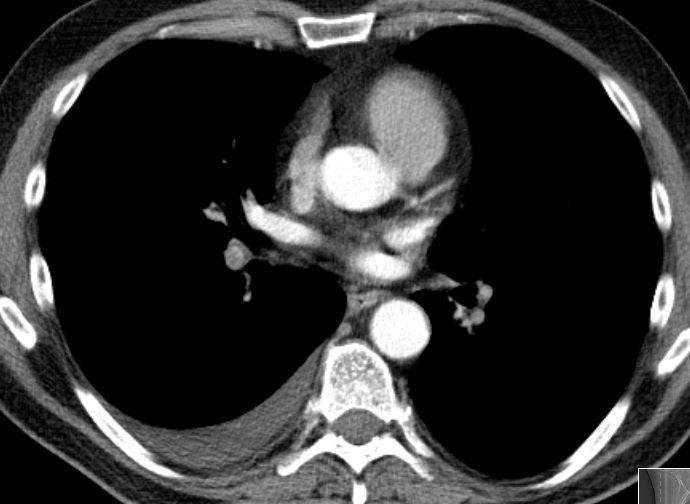

| Fallbeispiel | 63-jähriger Mann, bei dem ein rechtsseitiger Pleuraergusses auffiel.

Im Oberbauch ein schmaler Aszitesrand um die Leber erkennbar. Histologisch epitheloides Pleuramesotheliom mit Peritonealbefall (im CT nicht erkennbar).